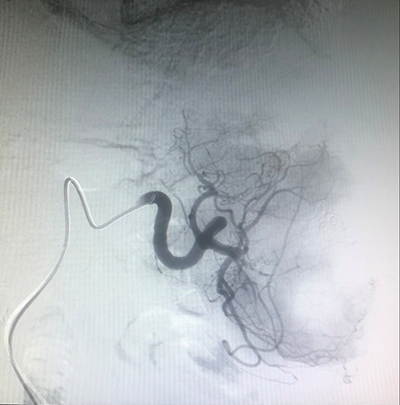

![]() | ![]() |

| (肺癌的介入治疗) | (盆腔恶性肿瘤的介入治疗) |